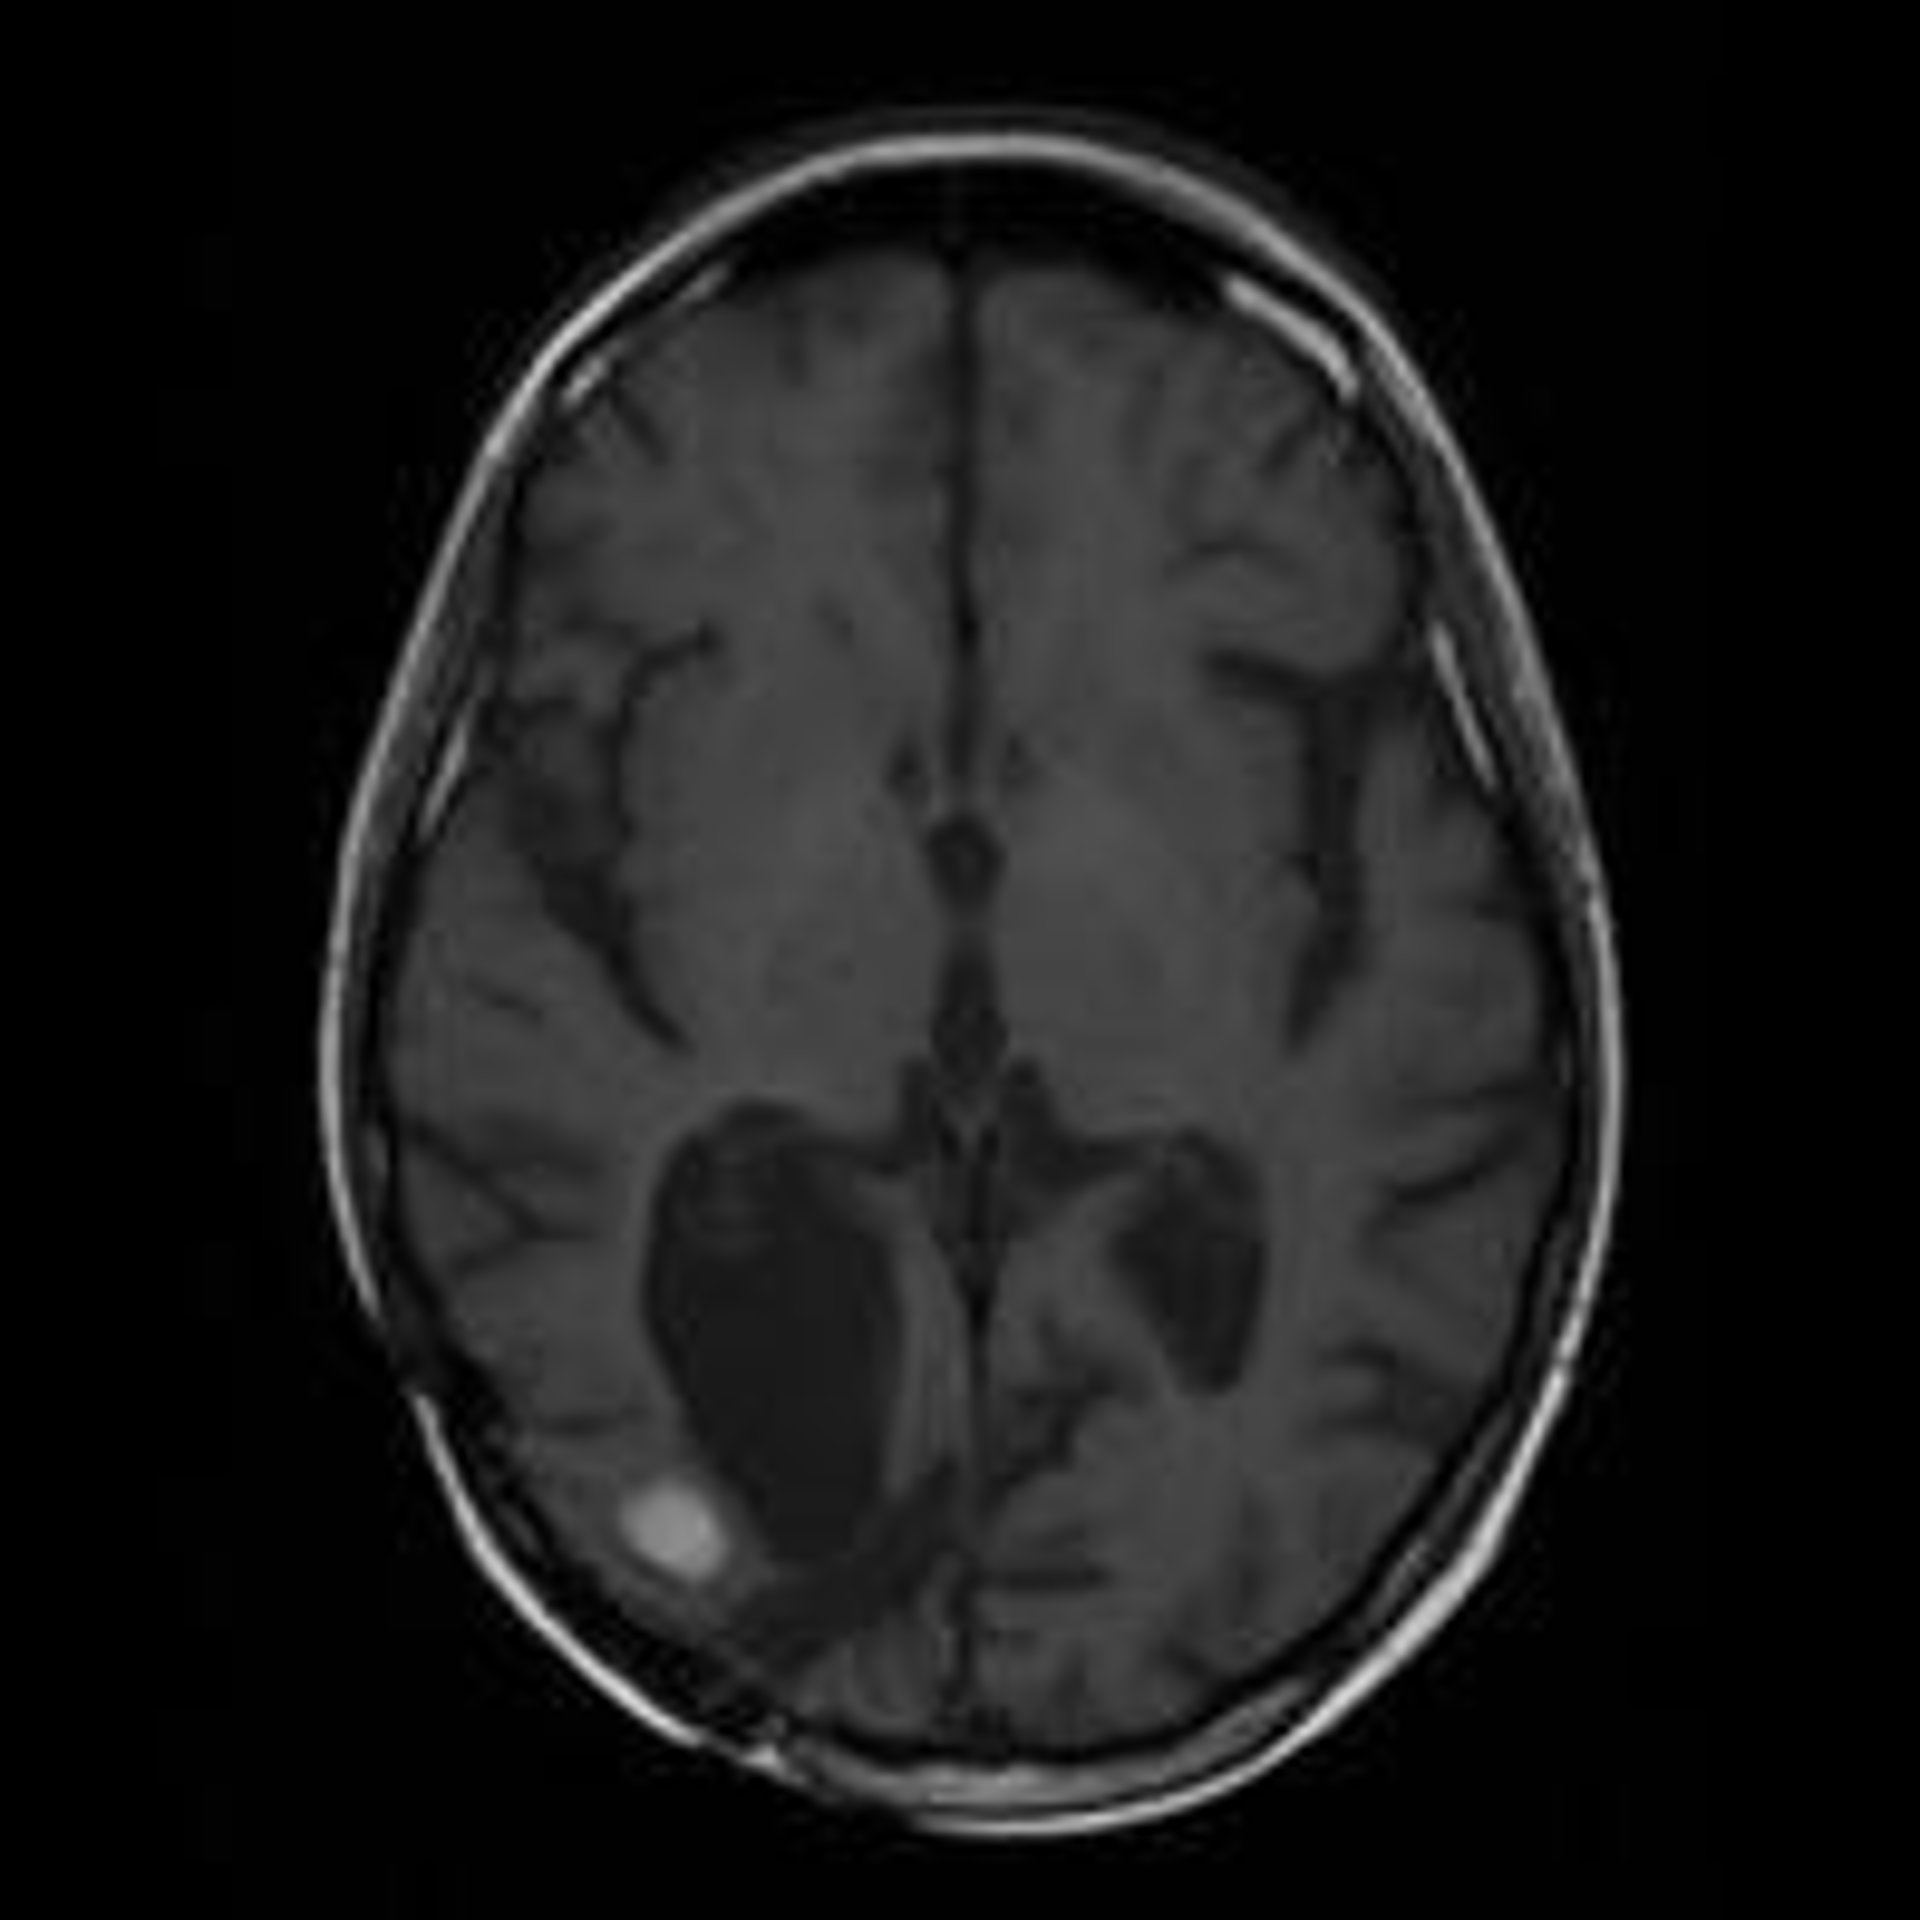

Un nuevo contraste mejora la visualización en resonancias magnéticas de tumores cerebrales

Resonancia Magnética De Un Cerebro Con Metástasis

Científicos del Instituto de Investigación Biomédica del Hospital Josep Trueta de Girona (Idibgi) han testado con éxito un nuevo contraste que mejora la visualización en resonancias magnéticas la extensión de los tumores cerebrales más agresivos.

Los científicos han comparado los resultados obtenidos entre el líquido de contraste convencional, el 'gadobutrol', con el 'gadofosveset', utilizado habitualmente para estudiar la aorta y los vasos ilíacos.

Los datos demuestran que el máximo nivel de información diagnóstica se logra seis horas después de haberse inyectado el contraste por vía intravenosa, cuando el tumor cerebral presenta "una definición no conseguida hasta ahora" y permite a los especialistas delimitar mejor su extensión.